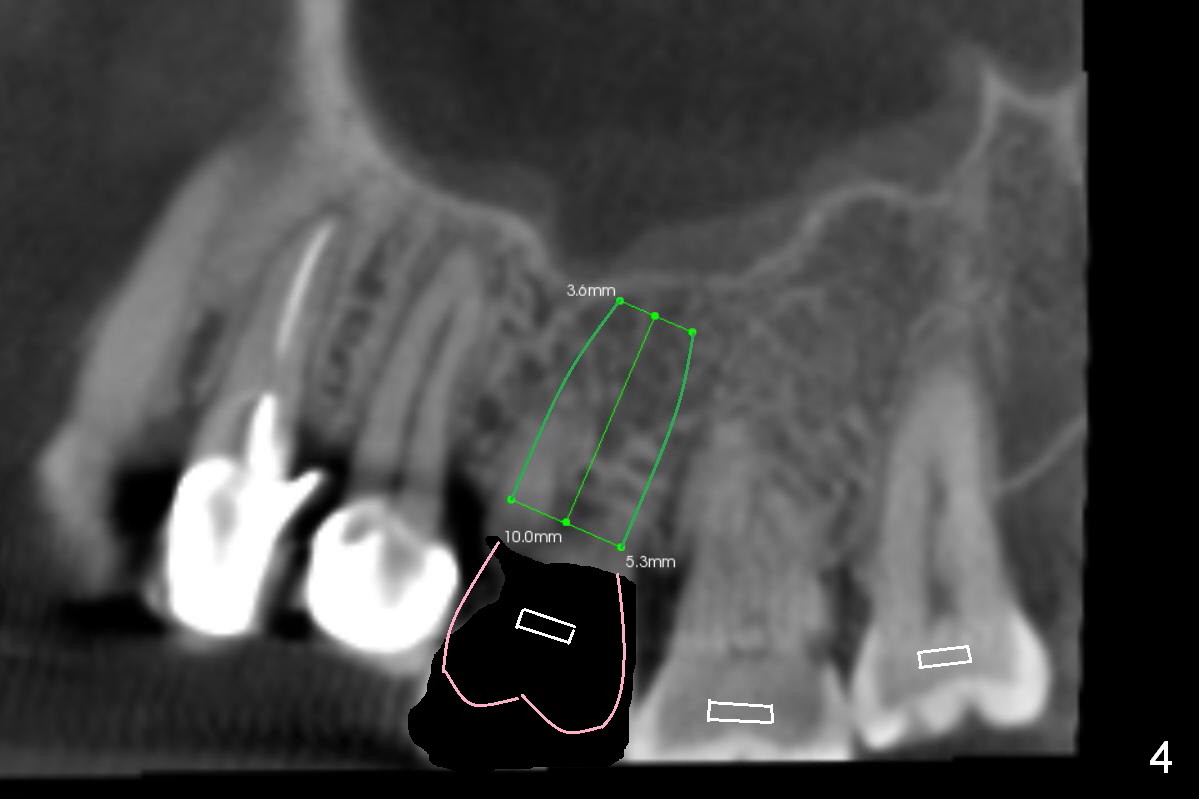

In addition to supraeruption of the teeth #2 and 3, the caries in the mesiobuccal root of #3 seems to be beyond salvation (Fig.1,2 arrowhead). When the implant at #3 is osteointegrated, a provisional restoration is placed (Fig.4 pink). Brackets (white boxes) are placed at differential levels among #1-3 to initiate regional orthodontic treatment using #3 as an anchorage. Mini-implants are placed if necessary. The tooth #1 is extracted after the limited ortho. Scaling & root planing will be done first.

Re-examination clinically and radiologically reveals that there is no caries involving the tooth #3 (Fig.5). It appears that CBCT may have artifact. Treatment planning for intrusion should be modified. Mini-implants will be employed after #2 DO composite. Prepare Anchor mini-implant kit, 2 of 10 mm and 1 of 8 mm mini-implants, anesthetics and #15 scalpel. Scaling & root planing will be performed.